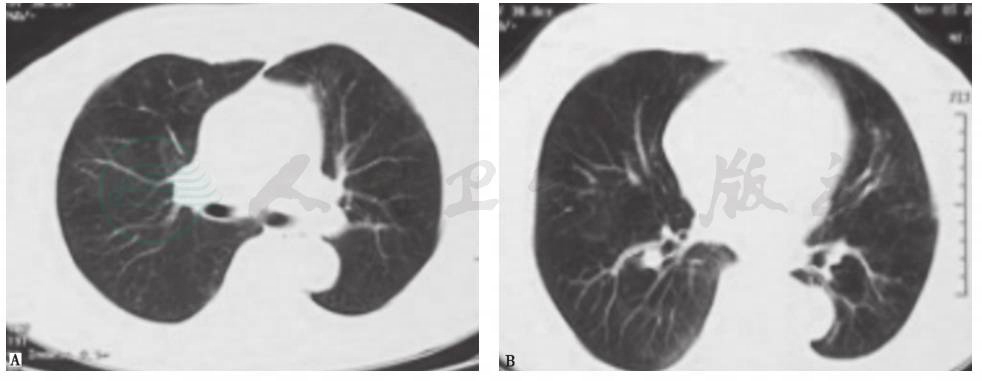

图5 肺曲霉菌感染胸部CT表现

女性患者,55岁,间断发热1个月,咳嗽1周,痰中带血1天,诊断为侵袭性肺曲霉菌病。胸部CT可见双肺多发结节影伴反晕征形成

肉芽肿性多血管炎(GPA):既往称为韦格纳肉芽肿,是一种坏死性肉芽肿性血管炎,属于自身免疫性疾病。该病主要侵犯上、下呼吸道和肾脏,通常以鼻黏膜和肺组织的局灶性肉芽肿性炎症为开始,继而进展为血管的弥漫性坏死性肉芽肿性炎症。临床常表现为鼻和鼻旁窦炎、肺病变和进行性肾衰竭,还可累及关节、眼、皮肤、心脏、神经系统及耳等。侵犯肺部时影像学表现可有多样性、多发性及多变性等特点(图6)。本例患者虽有蛋白尿的肾脏损害表现,但临床病程及症状与GPA相距甚远,故考虑GPA可能性不大。

图6 韦格纳肉芽肿胸部CT表现

女性患者,21岁,间断咳嗽2个月,诊断为韦格纳肉芽肿。胸部CT可见双肺多发结节影伴空洞形成,各结节影与血管关系密切